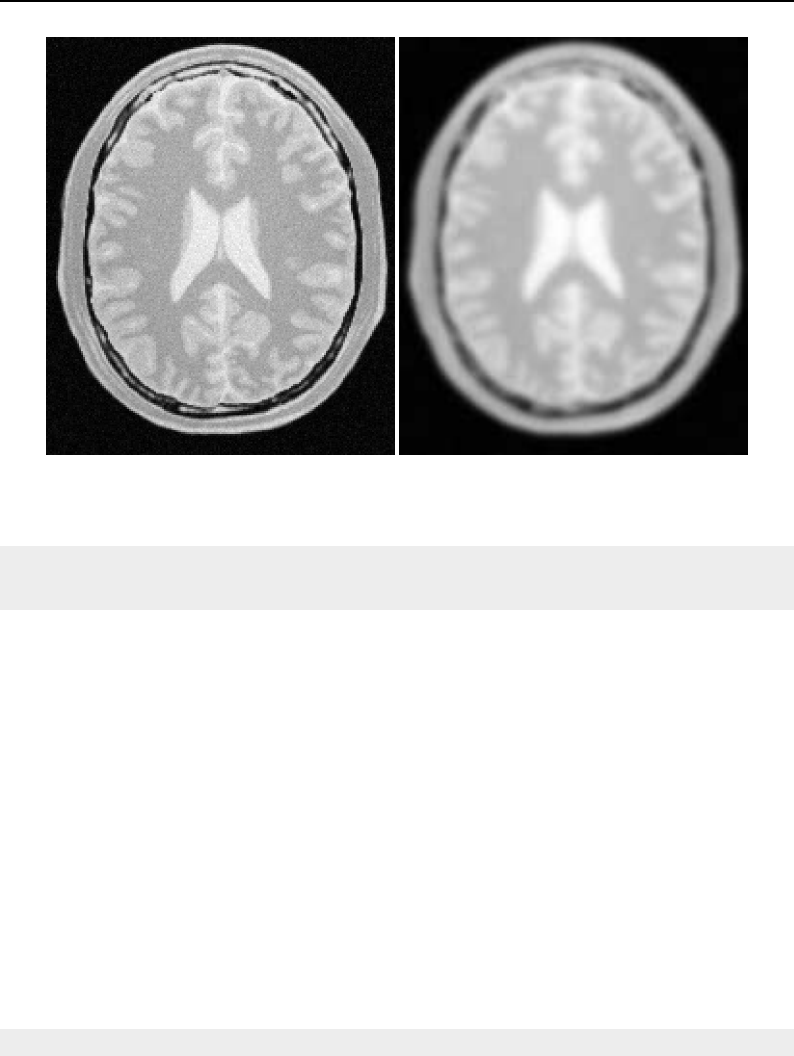

The National Library of Medicine Insight Segmentation and Registration Toolkit, shortened as the

Insight Toolkit (ITK), is an open-source software toolkit for performing registration and segmenta-

tion. Segmentation is the process of identifying and classifying data found in a digitally sampled

representation. Typically the sampled representation is an image acquired from such medical instru-

mentation as CT or MRI scanners. Registration is the task of aligning or developing correspondences

between data. For example, in the medical environment, a CT scan may be aligned with a MRI scan

in order to combine the information contained in both.